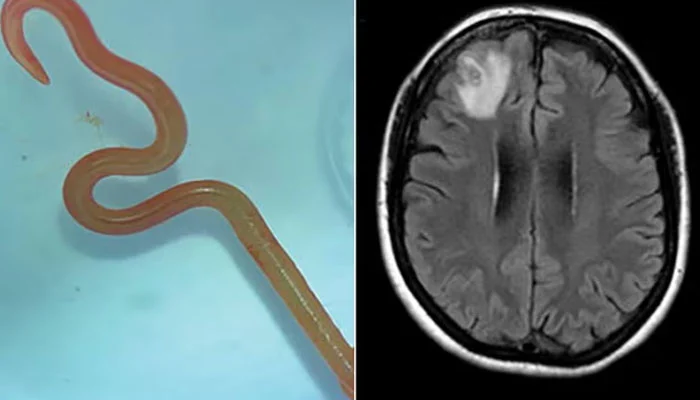

An unprecedented discovery has shocked the medical community as a live snake roundworm was extracted from the brain of a 64-year-old woman in south-eastern New South Wales. The remarkable finding came to light during a complex surgery at Canberra Hospital led by neurosurgeon Dr. Hari Priya Bandi. The patient had been experiencing a series of symptoms including abdominal pain, fever, and neurological issues, prompting the surgery. Dr. Bandi was shocked when she successfully removed an 8cm-long parasitic roundworm from the patient’s brain.

The medical team at Canberra Hospital collaborated to determine the best course of action for the patient. Their extensive research failed to uncover a similar case, prompting them to consult a specialized CSIRO scientist familiar with parasites. The live worm was identified as the Ophidascaris robertsi roundworm, typically found in pythons. Remarkably, this marked the first instance of this parasite being found in humans.